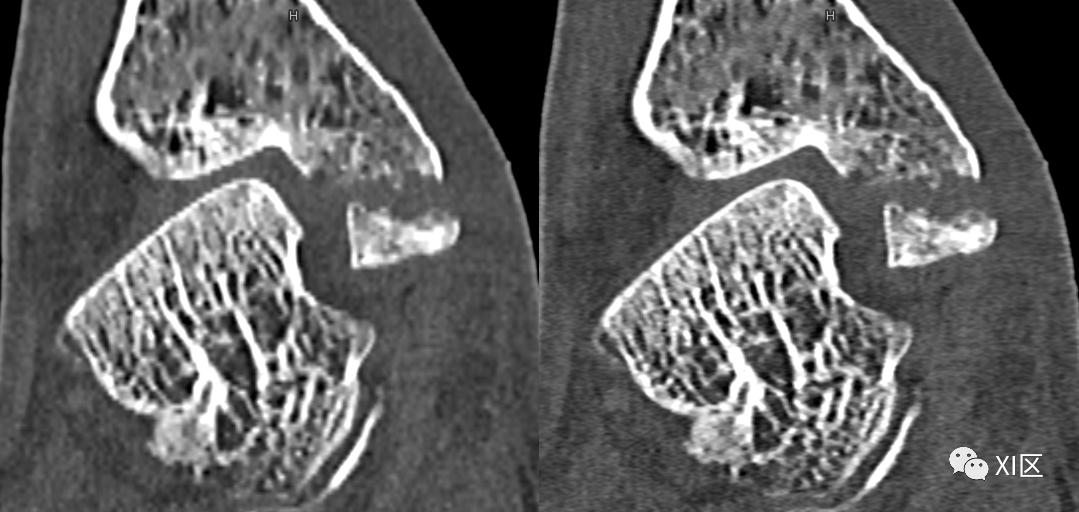

SOMATOM Definition Flash光子CT常规重建0.6 mm(128x0.6 mm)图像(左)与IVR重建0.6 mm(384x0.6 mm)图像(右)比较。使用IVR技术的图像关节面更平滑,骨小梁及骨折细节显示更清晰。

SOMATOM Force CT常规重建0.6 mm(192x0.6 mm)图像(左)与IVR重建0.6 mm(288x0.6 mm)图像(中)0.6 mm(576x0.6 mm)比较(上排:全局视图;下排:局部放大显示)。使用IVR技术的图像关节面更平滑,骨小梁及骨折细节显示更清晰。